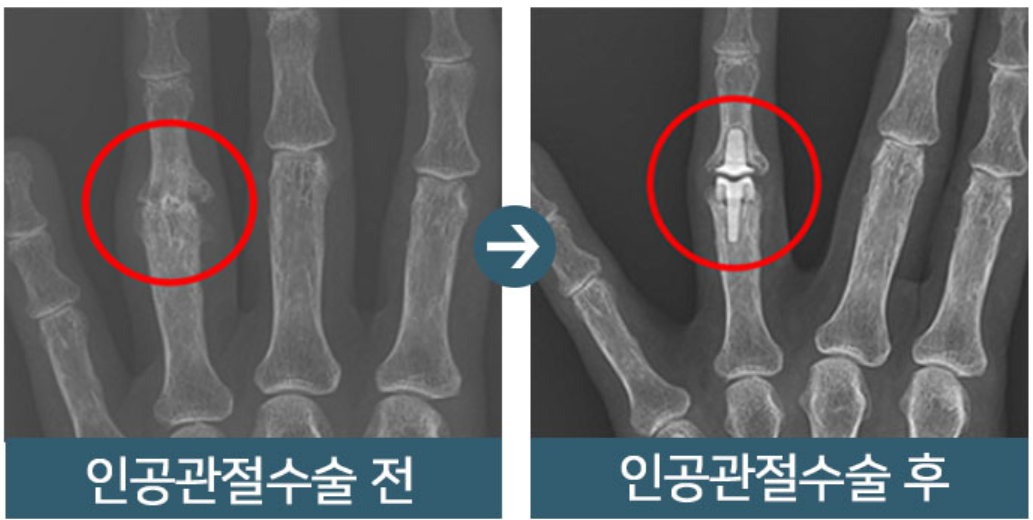

손가락 관절염 치료법은 직접적인 손가락에 시술을 하기 보다는 약물을 통한 염증 치료와 증상을 완화하는 형태의 치료로 진행됩니다. 다만 류마티스 관절염 같은 경우는 외과적인 치료가 아니라 면역계의 문제로 보기 때문에 스테로이드제를 동반한 치료가 진행되며 관절염으로 정형외과를 방문했더라도 차도가 없다면 류마티스로 특화된 류마티스 전문의를 만나 헐액검사를 포함한 전반적인 검사를 받는 것이 중요합니다.

또한 퇴행성 관절염인 경우에도 비수술적 치료를 진행하는 것이 필수적인데 관절 노화 외상이 이유가 되기 때문에 검사를 통해 약물 치료와 물리 치료로 우선 치료를 받고 통증이 가시지 않는다면 수술을 받아야 합니다. 하지만, 퇴행성 관절염의 경우 오랜 사용과 반복되는 부담으로 인하여 연골이 닳고 뼈가 변형이 이미 되어 있기 때문에 어떤 형태로 통증이 나타나느냐에 따라 다른 치료방식이 도입되는 것이 특징입니다.